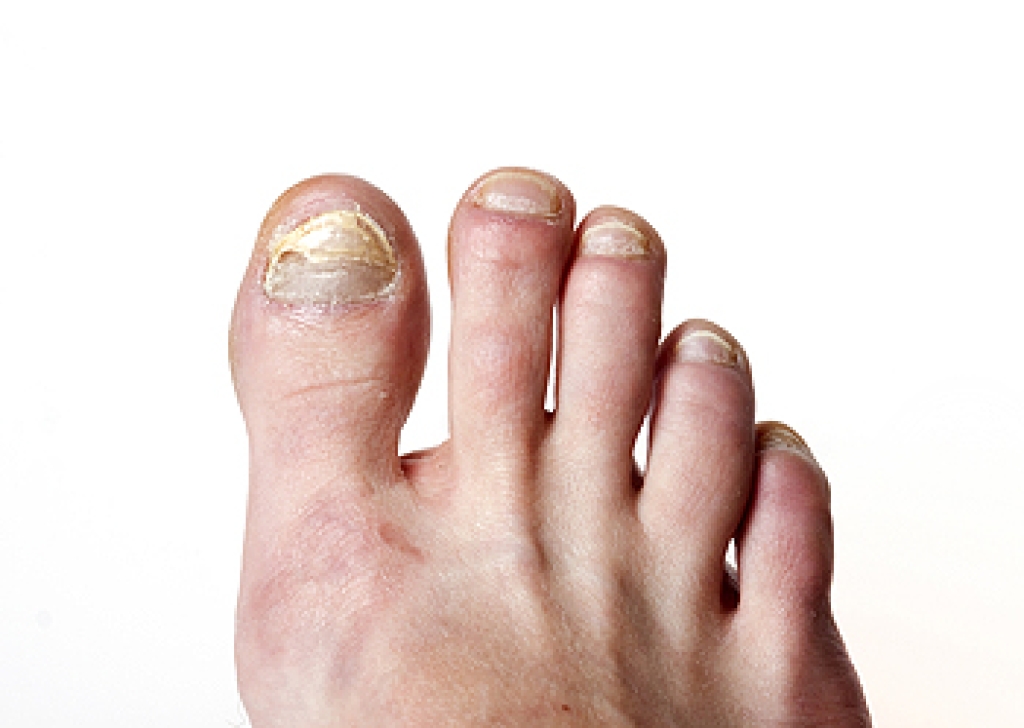

Maffucci syndrome - This affects the long bones in a child’s foot leading to the development of abnormal bone lesions. They are benign growths and typically develop in early childhood and the bones may be susceptible to breaking.